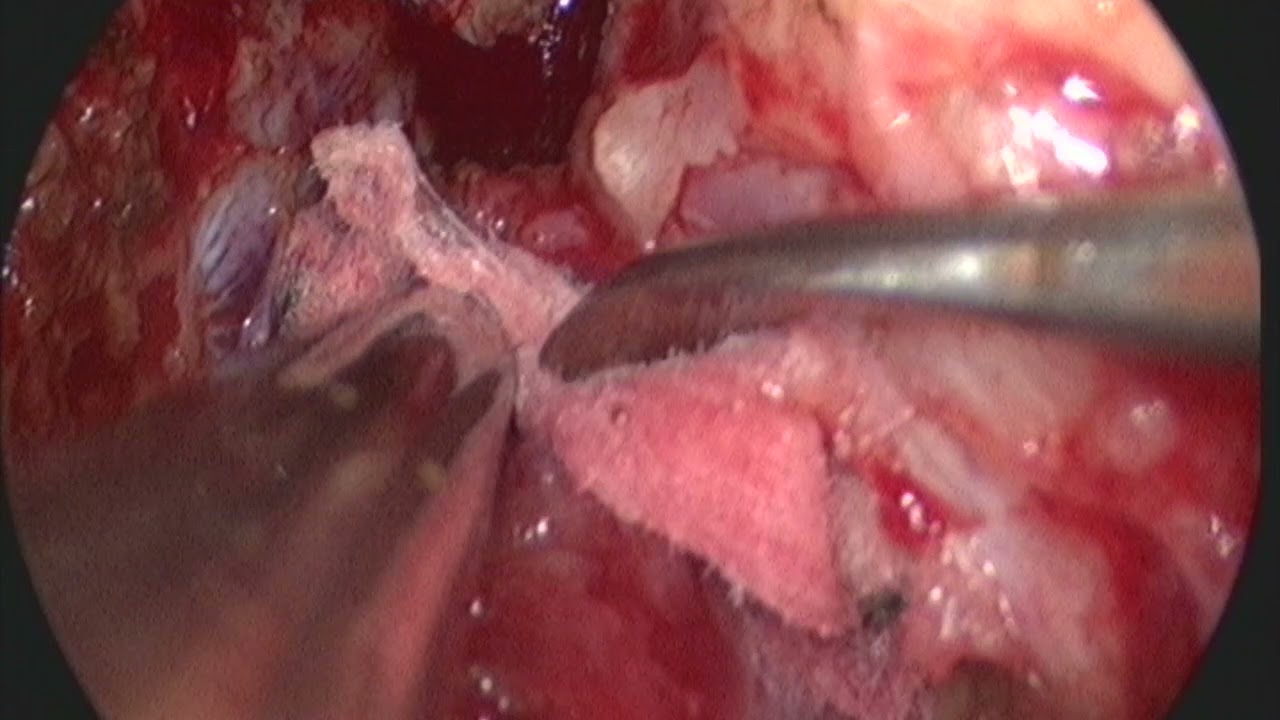

Atuando exclusivamente na área de neuro oncologia realiza diversos procedimentos de cirurgias para meningiomas, Gliomas e Tumores Hipofisários. Atuando como preceptor do serviço de Neurocirurgia do FBHC é responsável por todas as cirurgias de Hipófise realizadas pelo SUS no estado de Sergipe.

- Cirurgia endoscópica

- Cirurgia da base do crânio

Microcirurgia Cerebral Endoscopica

Microcirurgia De Tumor Cerebral